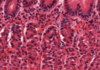

Which of the statements concerning the image above is TRUE?

- The cells with eosinophilic cytoplasm are a simple columnar epithelium

- The cells with eosinophilic cytoplasm are ciliated

- The cells with eosinophilic cytoplasm have a secretory function

- The cells with haematoxyphilic cytoplasm have a secretory function

- This is a sample from the large intestine

4.The cells with haematoxyphilic cytoplasm have a secretory function. The cells with eosinophilic cytoplasm in the centre of the image are forming a simple cuboidal epithelium and they are lining a duct within a salivary gland. They are not ciliated and do not have a secretory function. The cells with abundant haematoxyphilic cytoplasm around the periphery of the image are secretory cells.